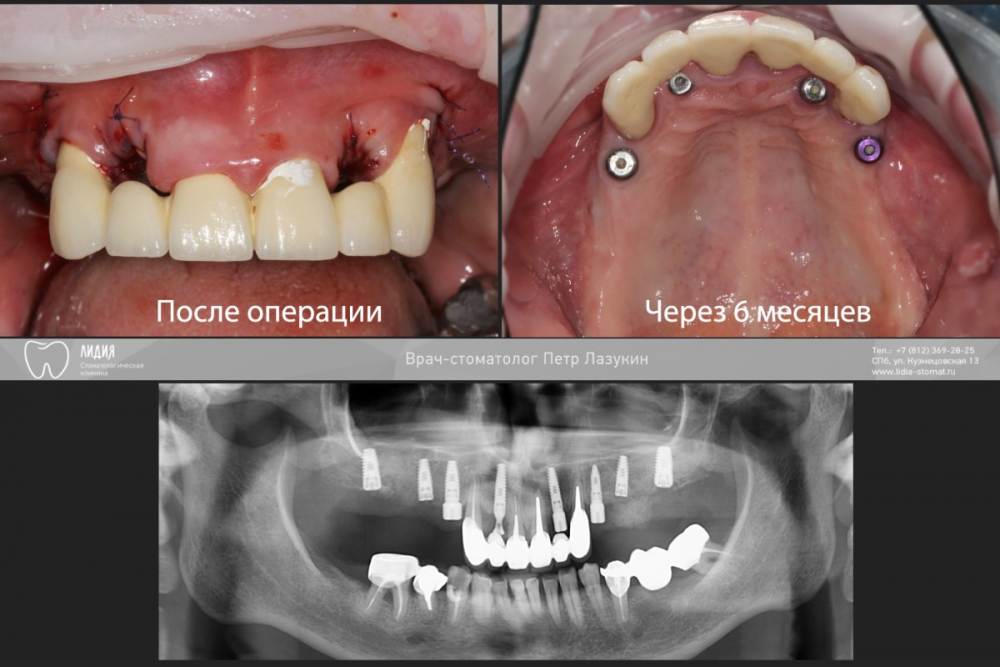

pit Опубликовано 5 октября, 2021 Поделиться Опубликовано 5 октября, 2021 Клинический случай. Старт работ в 2015 году. План простой: Полная дуга, верхняя челюсть. Начали в 2015, закончили в 2021. Какой был план? Зубы в/ч все под удаление. Фронт был временно сохранен для временного протезирования. Установлены импланты с костнопластическими манипуляциями. В качестве временных коронок использованы металлокерамические коронки. Следующим этапом, после интеграции, было открытие имплантов и изготовление временных коронок. И тут пациент пропал на 2 года, а затем еще на четыре)))). Лишь поломка времянок, через 6 лет, сподвигла пациента обратиться за изготовлением постоянных коронок. Протокол и комменты в слайдах. КТ после протезирования. 11.mov 1 2 2 Ссылка на комментарий